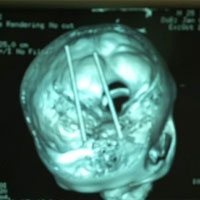

Tuyệt vọng và hoảng sợ, cô Irene tới viện làm xét nghiệm máu, chụp não và làm điện não đồ nhưng các xét nghiệm đều không giúp phát hiện ra nguồn bệnh. Chỉ đến khi bác sĩ quyết định kiểm tra da đầu, dưới những lọn tóc vừa nối và phát hiện não bộ cô Irene đang bị giòi xâm nhập.

Các bác sĩ nghi ngờ rằng, số tóc nối đó bị lấy từ cơ thể người chết và những con giòi được phát triển từ ổ trứng nằm trên những lọn tóc nối. Để chữa dứt điểm căn bệnh đau đầu do giòi gây ra, cô Irene đã phải cạo trọc đầu và điều trị kháng sinh trong vòng 2 tuần.